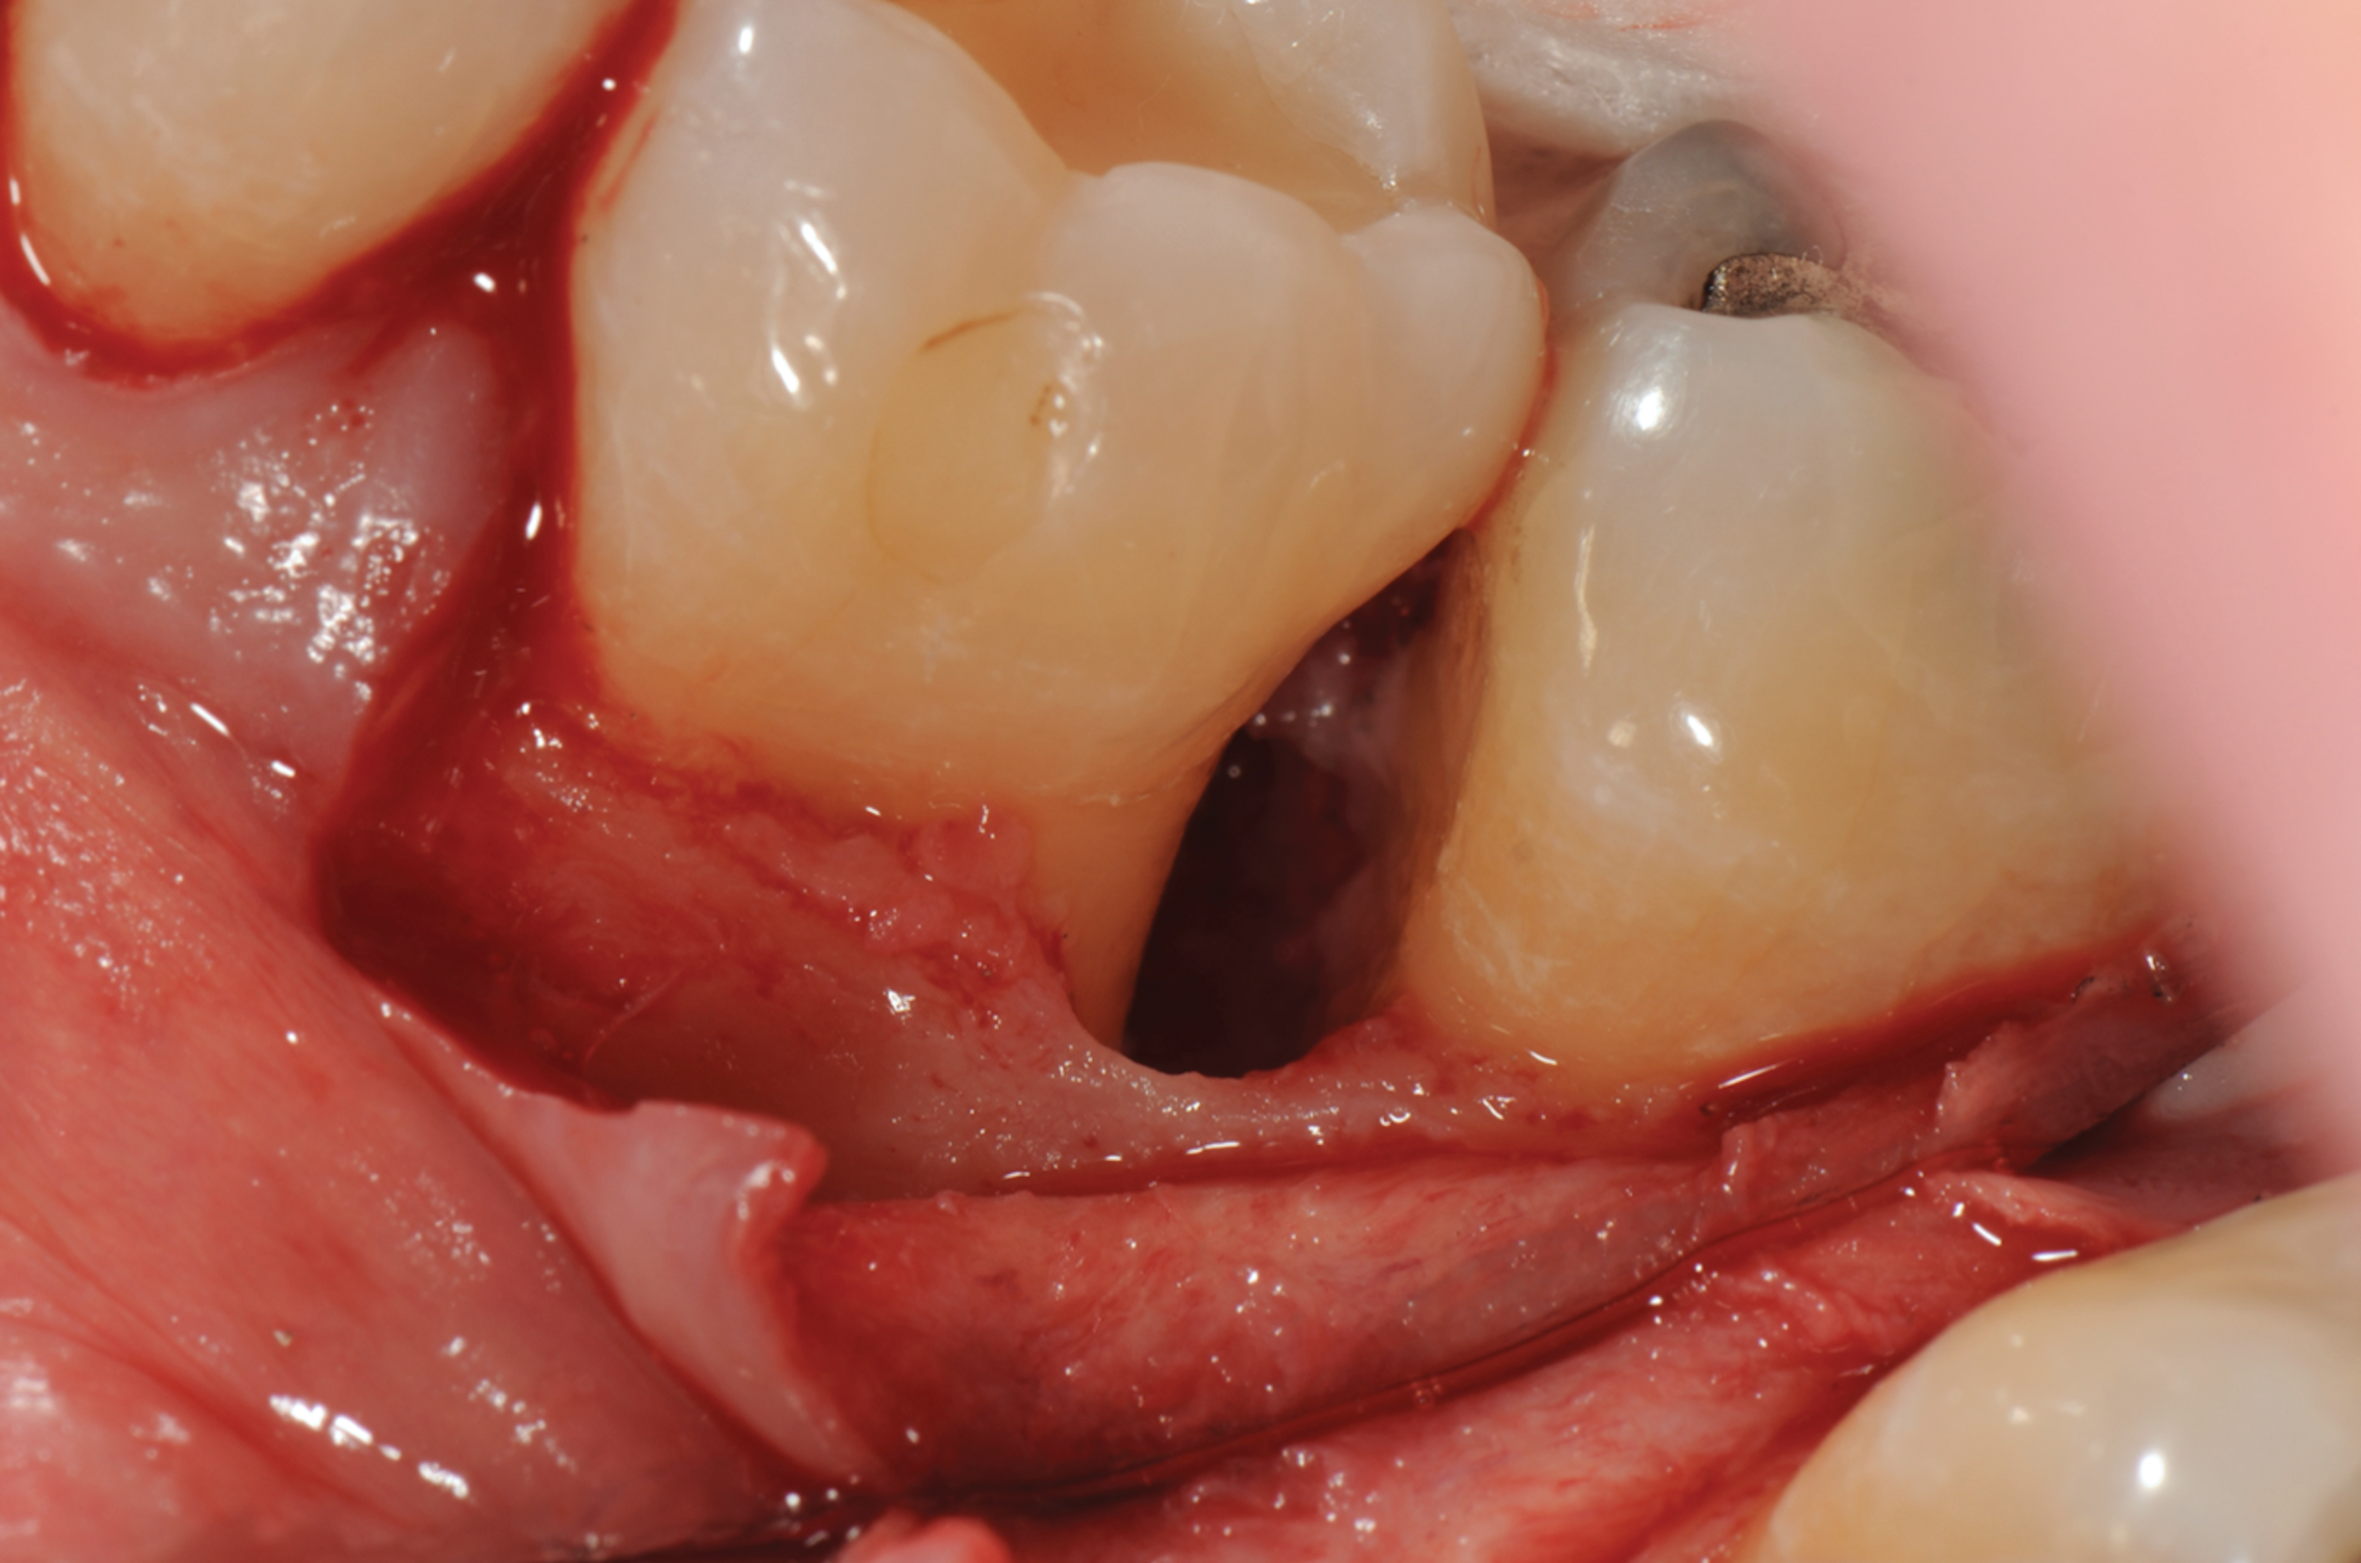

Fig 3. Distal probing depth of 10 mm at tooth No. 19.

Figure 3

In the case presented, a 56-year-old healthy nonsmoking male patient, diagnosed with periodontitis stage III, localized, grade B, had been under care in a private practice periodontal office (RAL) for 25 years. He had a history of good compliance with his treatment (full-mouth plaque score <20%). During the COVID-19 pandemic, the patient missed three supportive periodontal therapy (SPT) visits over a year, resulting in periodontal breakdown interproximal between teeth Nos. 18 and 19 (mandibular left second and first molars, respectively). At his most recent periodontal maintenance visit, significantly increased periodontal probing depths of up to 10 mm with bleeding on probing were noted (Figure 1 through Figure 3). The periapical radiograph revealed a deep, narrow three-wall intrabony defect at the distal aspect of tooth No. 19, with class I buccal furcation involvement (Figure 4). According to the periodontal risk score (PRS),15 formerly known as the Miller-McEntire periodontal prognosis index, the tooth prognosis at the patient's initial examination was "good" (score = 5), taking into account that he was unaware of his hemoglobin A1C (HbA1c) levels. This scoring motivated the patient to be tested, and his follow-up HbA1c was <6%, thus reducing his PRS to 3, which was considered "excellent," as the PRS target goal for regenerative procedures is a score of <5.15